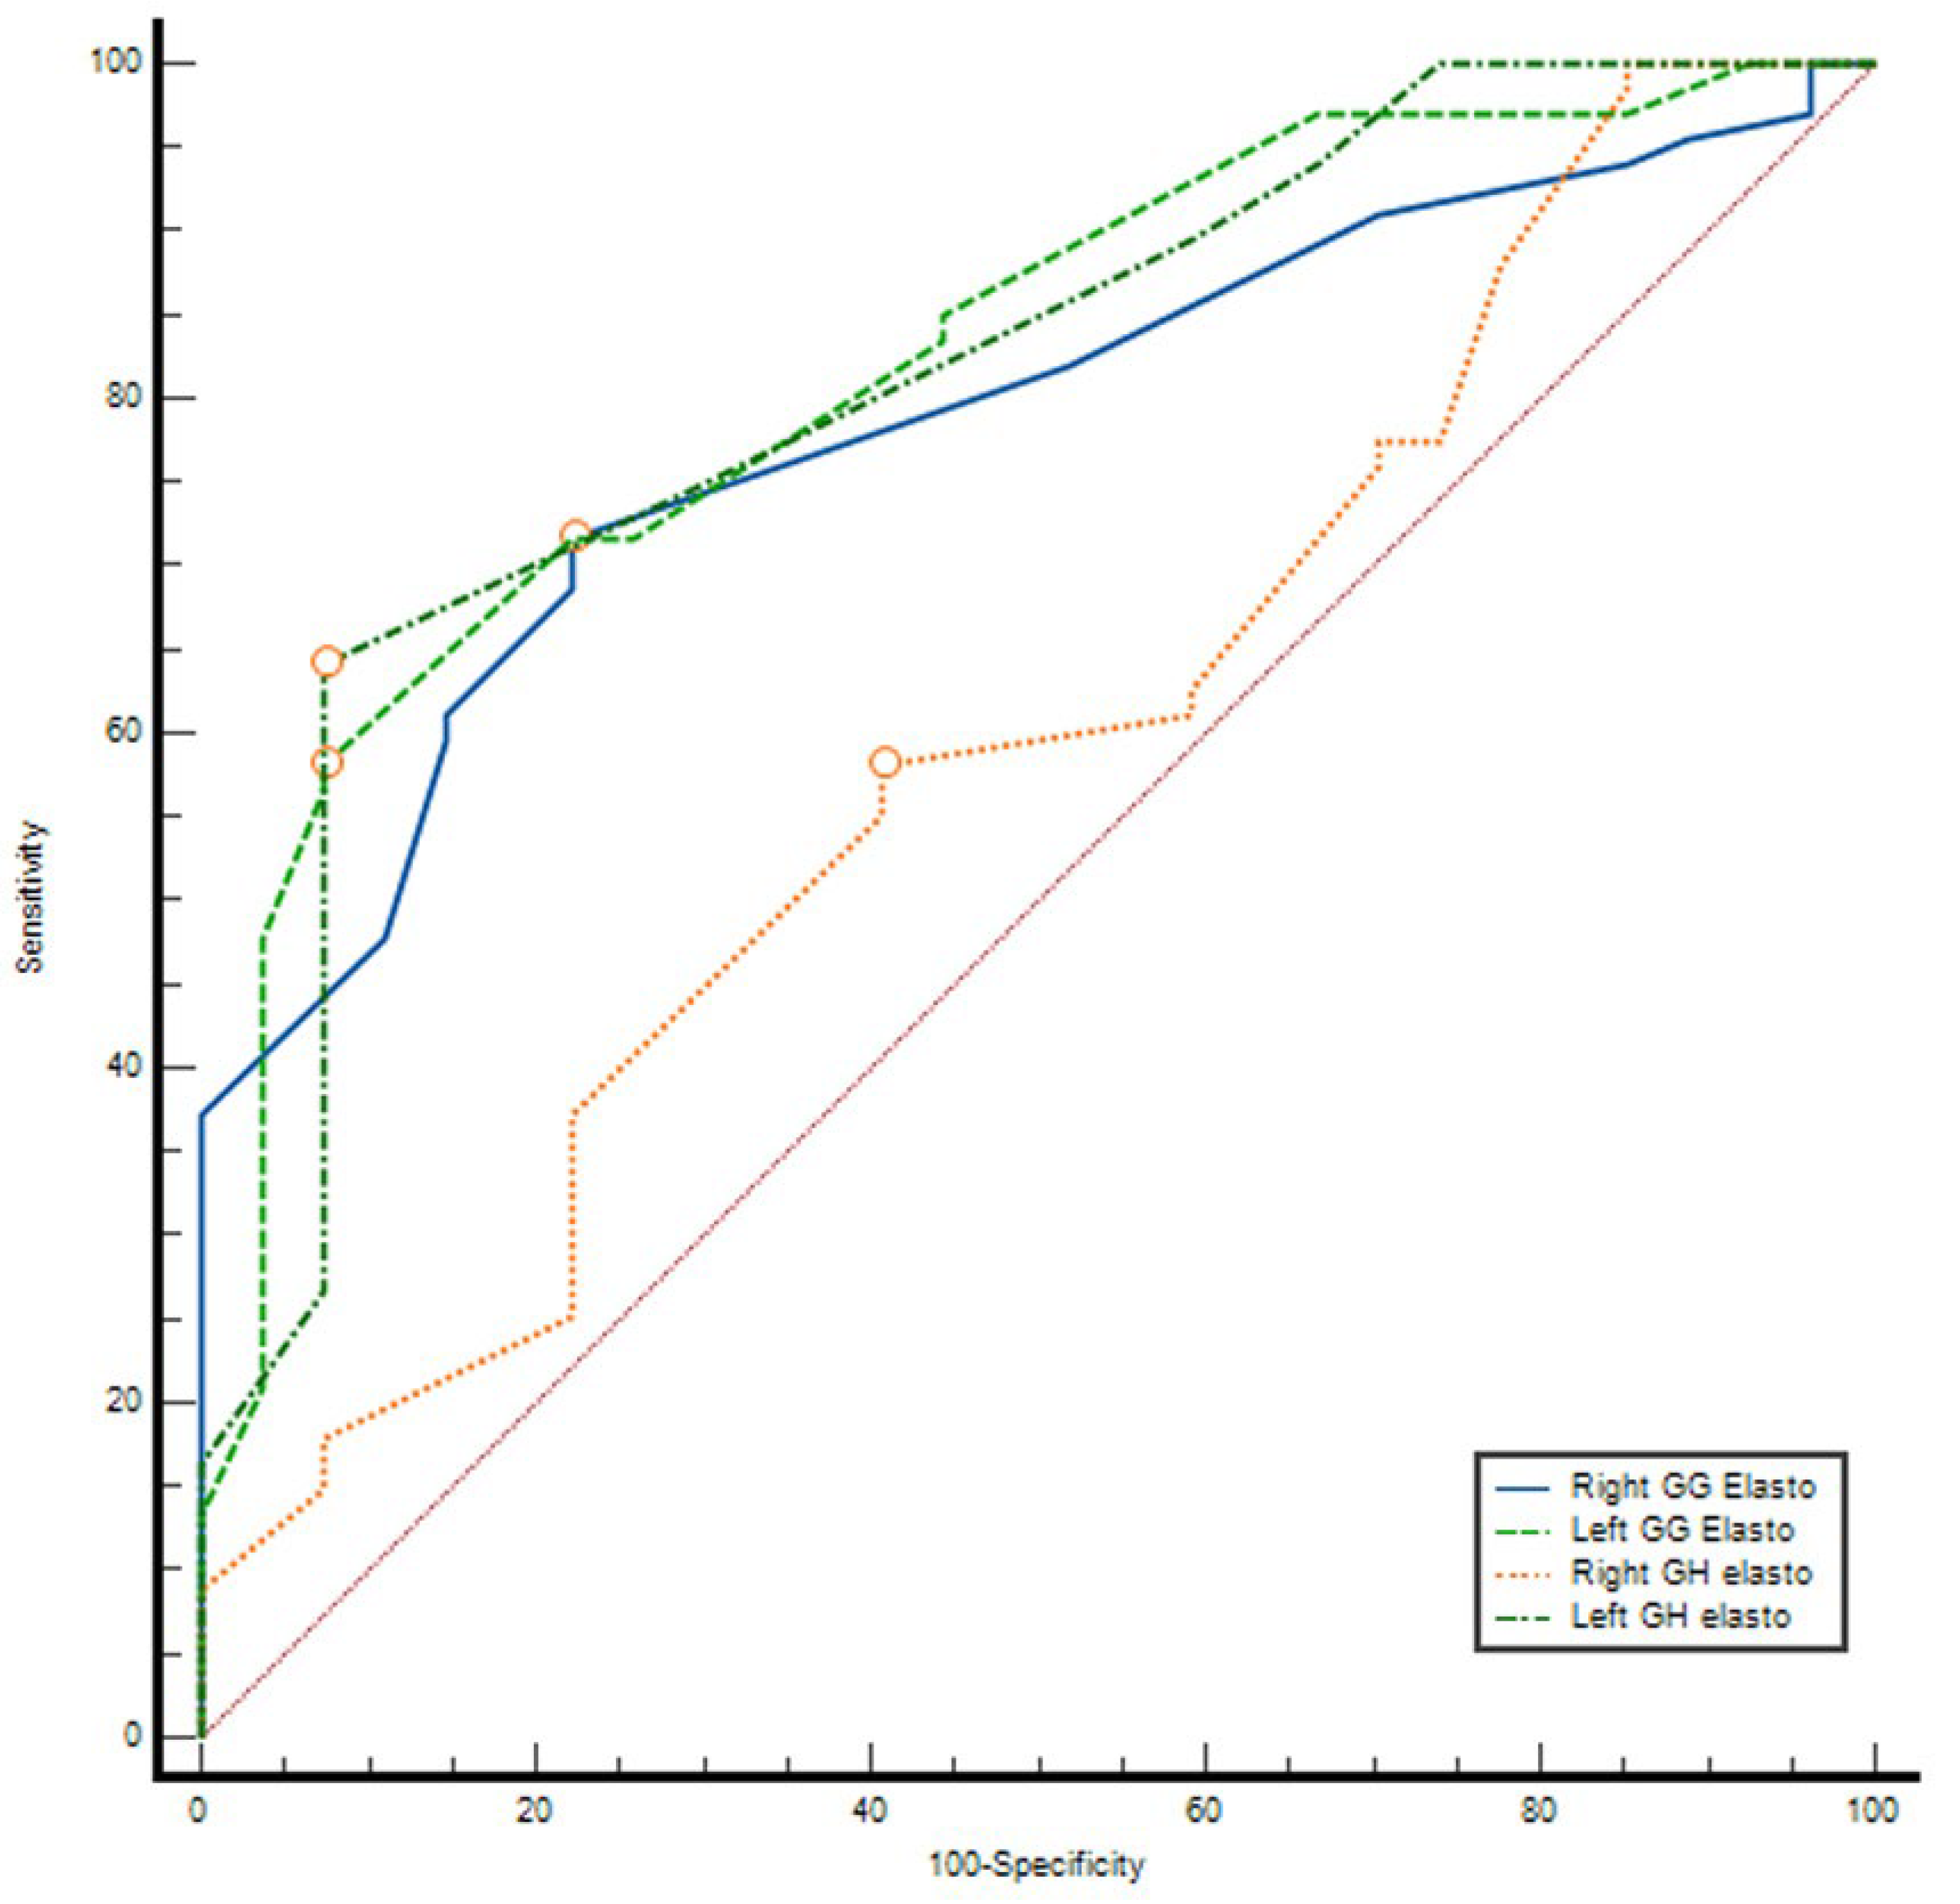

3.3. ROC Curve Analysis

ROC analysis demonstrated that elastography parameters had variable diagnostic accuracy for distinguishing between groups. The AUC values were 0.591 (95% CI: 0.464–0.718,

p = 0.169) for right GH elasto, 0.784 (95% CI: 0.691–0.877,

p < 0.001) for right GG elasto, 0.813 (95% CI: 0.718–0.907,

p < 0.001) for left GH elasto, and 0.821 (95% CI: 0.731–0.911,

p < 0.001) for left GG elasto. The optimal cut-off values determined by the Youden index were 2.61 m/s, 2.525 m/s, 2.605 m/s, and 2.63 m/s, respectively. At these thresholds, sensitivity ranged between 58.2 and 71.6% and specificity between 59.3 and 92.6%. The highest discriminatory performances were observed for left GH elasto (AUC = 0.813) and left GG elasto (AUC = 0.821), with PPV values exceeding 95% and NPV ranging between 47 and 52% (

Table 6) (

Figure 2).